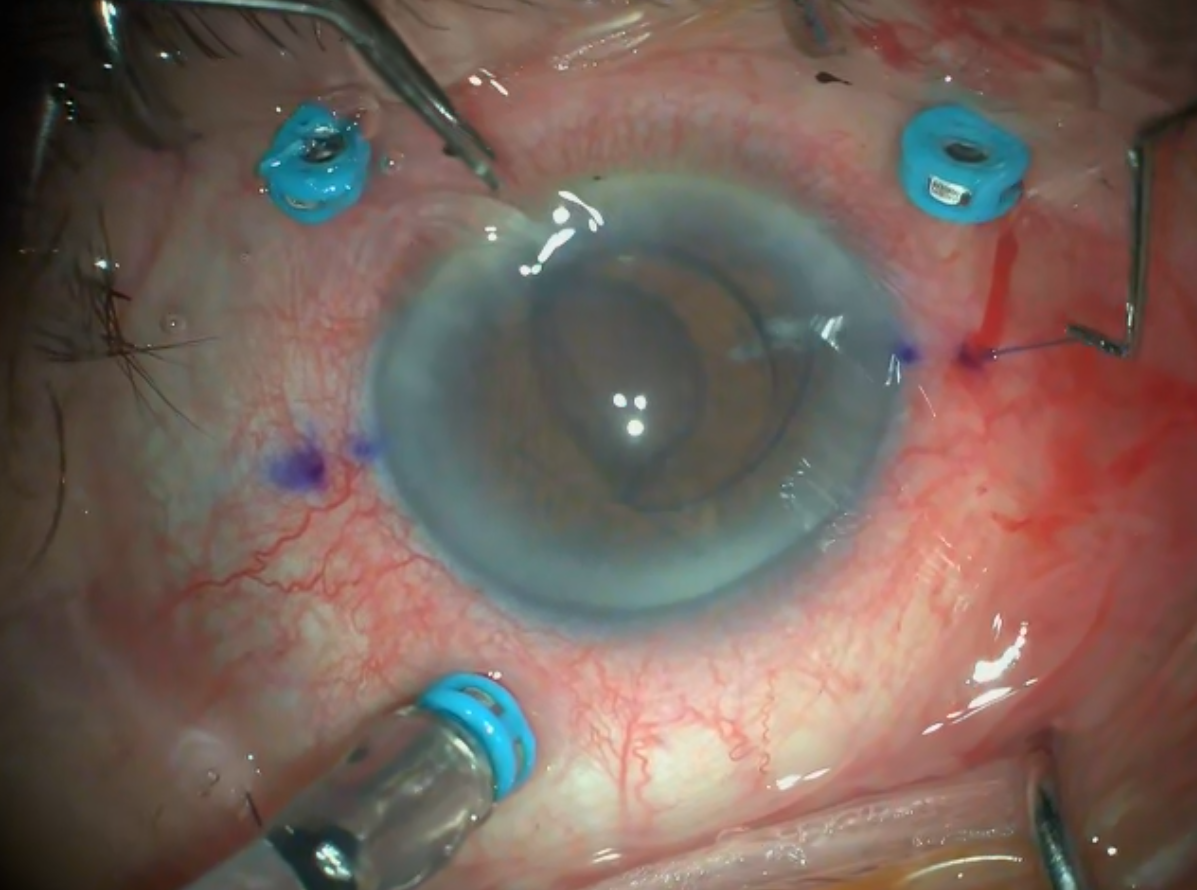

2026 Nisan Ayın Videosu

Travmatik Tek Taraflı İOL Dislokasyonunda Sağlam Skleral Fiksasyonun Korunması i ...

Devamı